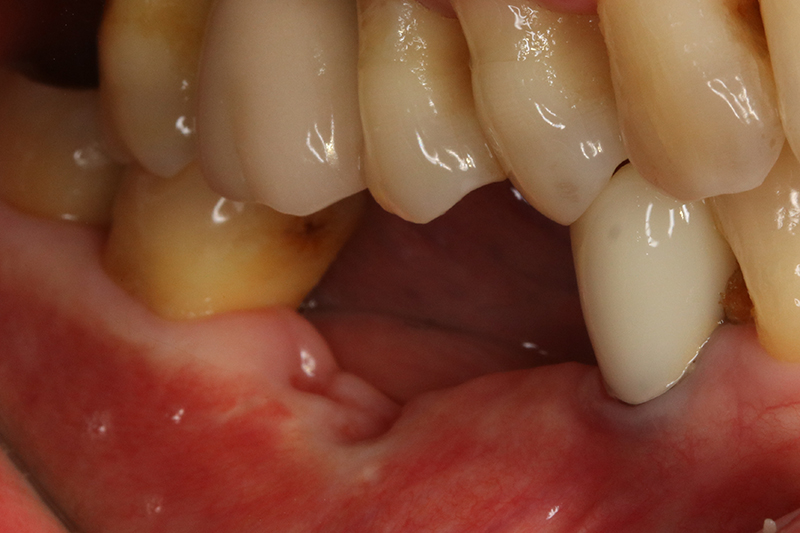

缺牙多顆

案例一

術前